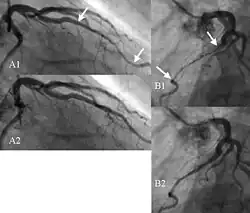

| Angiogram showing myocardial bridging resulting in arterial compression. | |